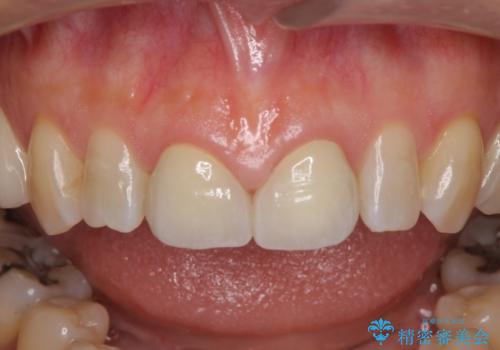

- 前歯のすきっぱを主訴にご来院された患者様です。他院でつめものやラミネートべニア(前歯の表面のみセラミックを貼り付ける)を行っていましたが、頻繁に外れることに悩まれており、クラウン(歯全体をセラミックがつつむ)をご希望されました。また、奥歯に大きな虫歯があり、歯が割れていたため、奥歯の治療も併せて行いました。

今回はまず欠けた場所を修復して見た目を回復させたのち、ラミネートべニアの仮歯をつくり、しばらく使用して考えて頂きました。メリットやデメリットを説明した結果、外れにくいセラミッククラウンをご選択頂きました。

咬み合わせや元のご自身の歯の色に特徴があったため、セラミッククラウンを修正したり、隣の歯を金属を外して白いつめものに変えたりして経過観察を長めに行いました。